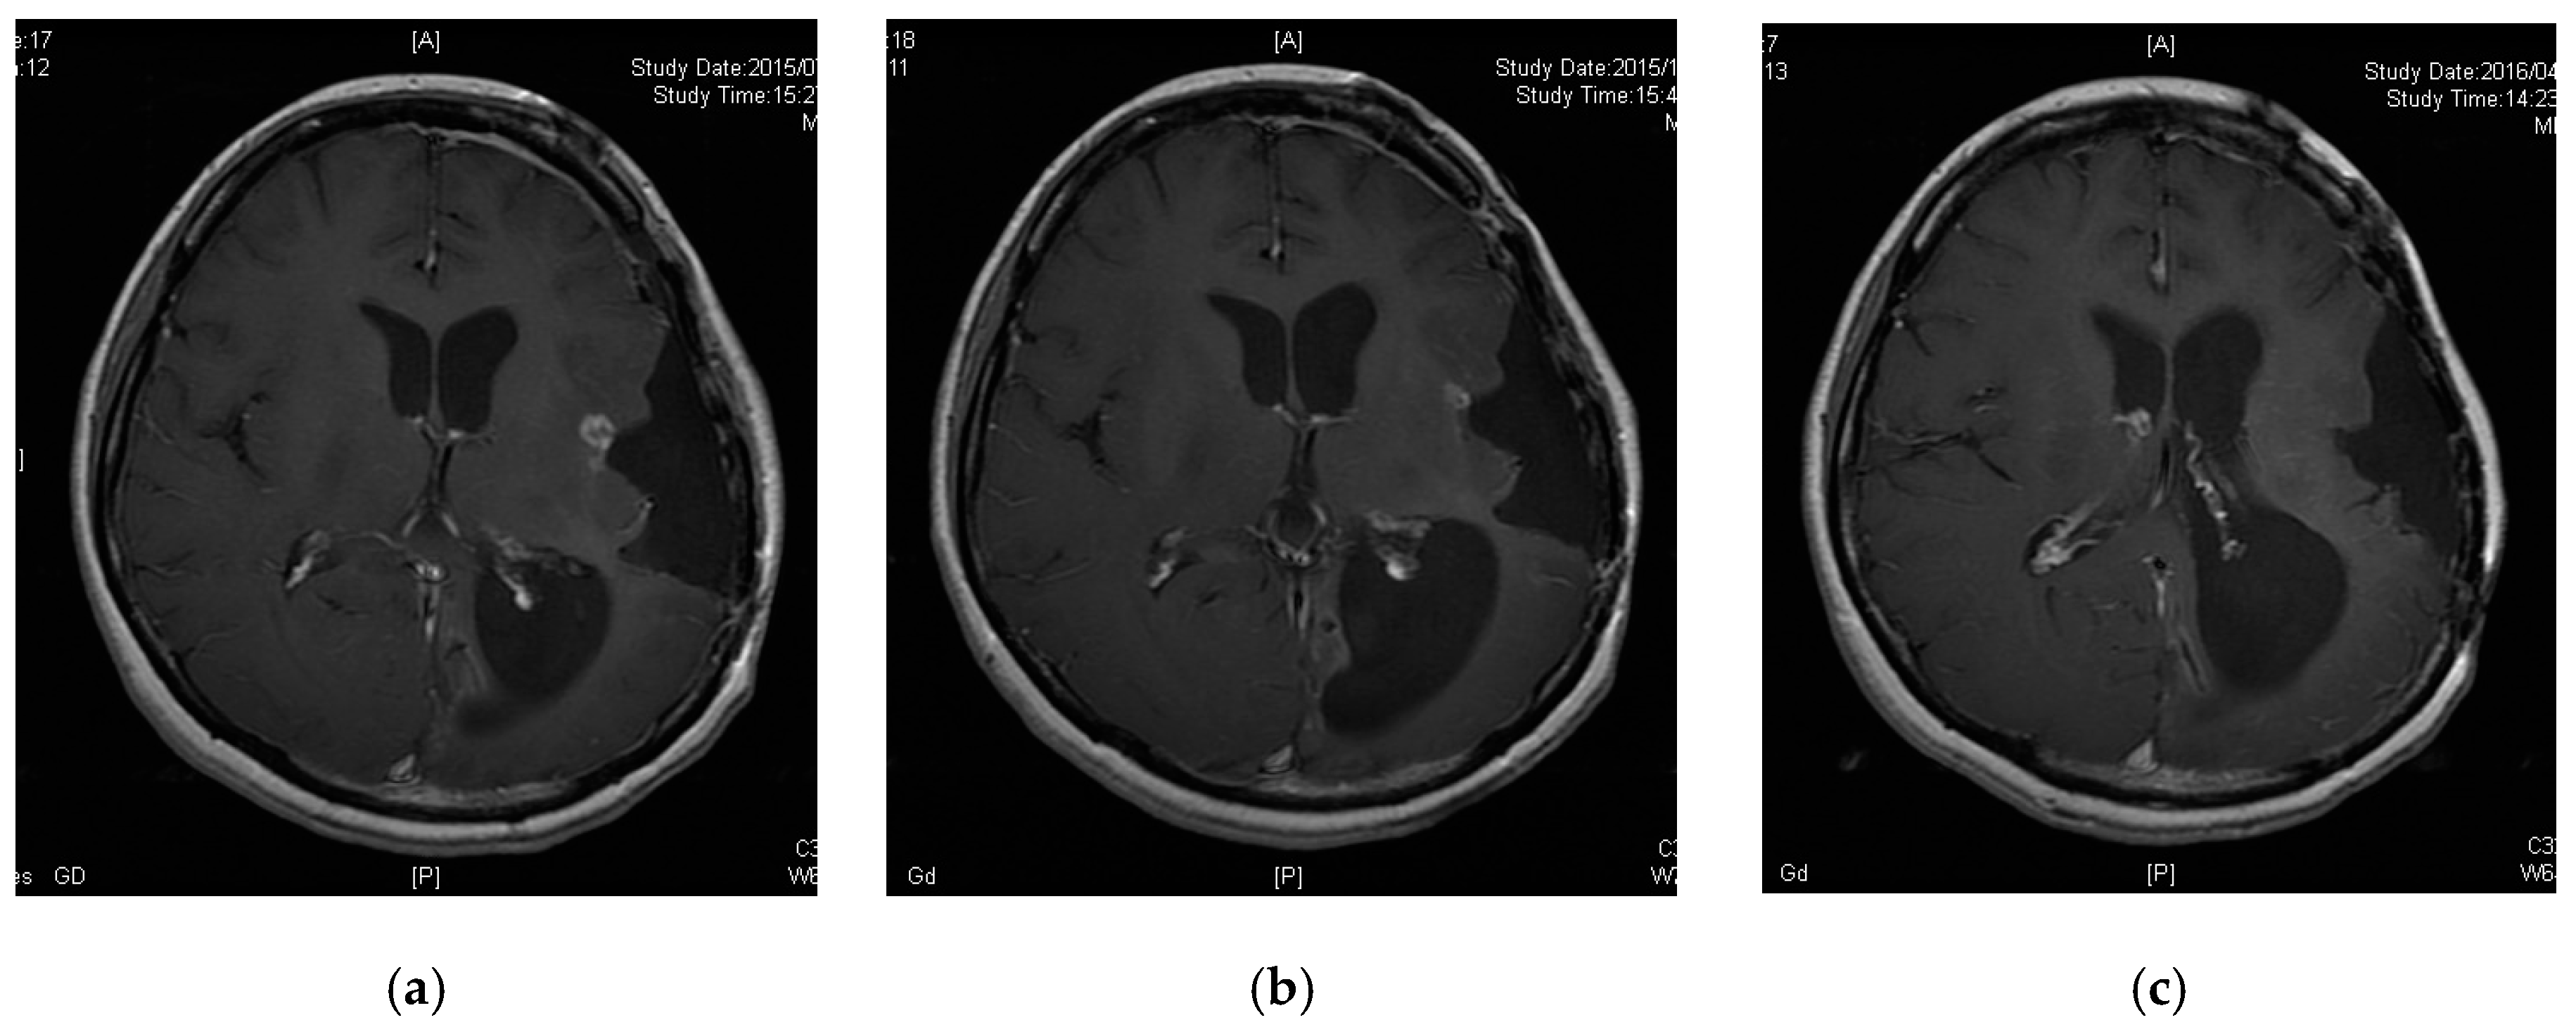

3.5. A Case of CR following Peptide Vaccination

| 6 | 20 | 37.5 | PR | PR * | 38.1 | 38.1 |